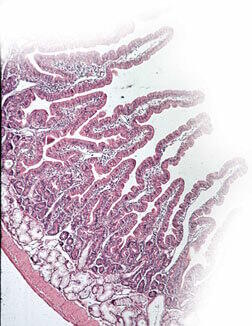

Les ulcères peptiques sont caractérisés par une érosion de la paroi mucosale du duodénum (ulcère du duodénum) ou de l'estomac (ulcère gastrique).

Le mécanisme par lequel la réglisse semble exercer son action bénéfique est lié à sa capacité à augmenter la production de prostaglandines dans les cellules endothéliales de l'estomac avec, pour résultat, un effet cyto-protecteur sur la muqueuse gastrique.